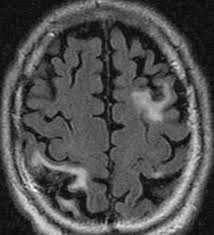

It is also called subcortical vascular dementia which damages the deep layers of the brains white matter. Illness or sickness in general. Mathers and colleagues 27 reviewed their experience with 20 cases showing white matter changes on CT scan which suggested a diagnosis of Binswangers disease.

What do we know about Binswangers disease. CADASIL cerebral autosomal dominant arteriopathy with subcortical infarcts and leukoencephalopathy is a hereditary small artery disease which is phenotypically similar to Binswangers disease BD a nonhereditary form of small artery disease. They concluded that Binswangers disease is probably due to chronic or acute-on-chronic white matter ischemia.